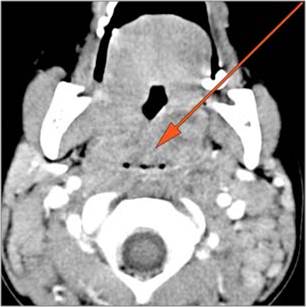

There is edema or abscess within the fat of the adjacent parapharyngeal and retropharyngeal space. [Yes/No]

There is edema or abscess within the adjacent parapharyngeal and retropharyngeal spaces. [Yes/No]